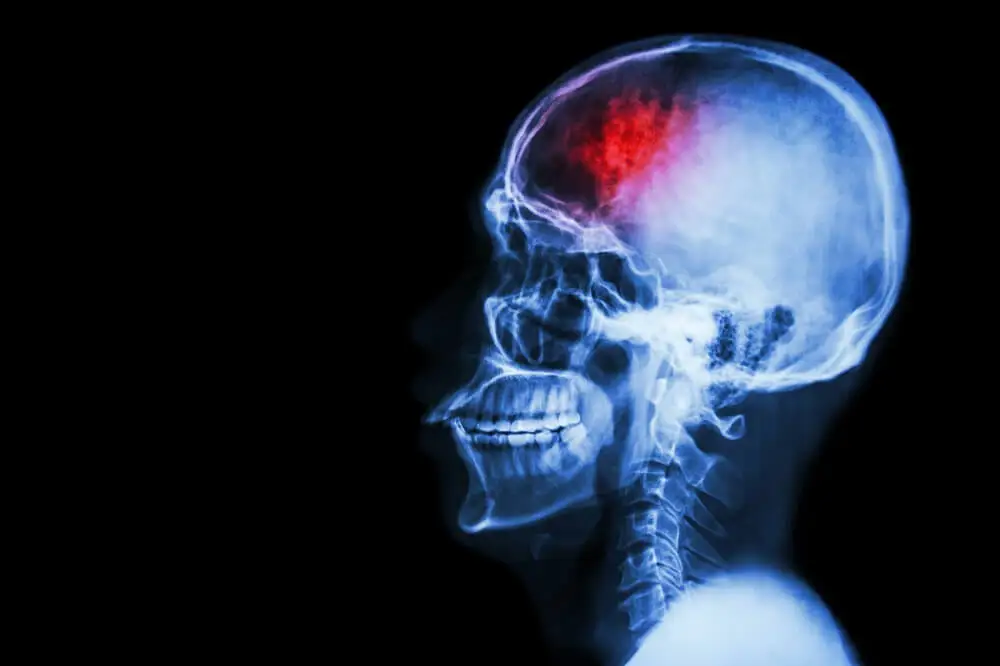

Linksseitige Kopfschmerzen können einen schwerwiegenderen Ursprung haben, wie zum Beispiel einen der nachfolgend genannten:

- Schlaganfall: Er wird durch eine Blutung im Gehirn oder durch ein Gerinnsel verursacht, das den Blutfluss in diesem Bereich blockiert. Zu den häufigsten Symptome gehören ziemlich starke, plötzlich auftretende Kopfschmerzen.

- Hirntumor: Dieser verursacht nicht immer spezifische Anzeichen. Allerdings kann er sich auch durch plötzliche, starke Kopfschmerzen bemerkbar machen.